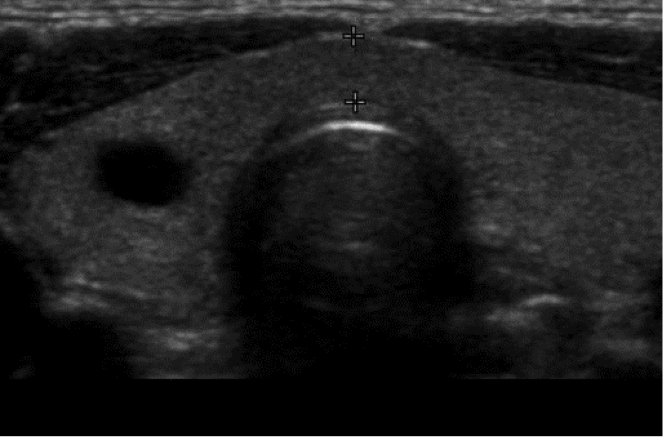

Dx?

Cystic nodule